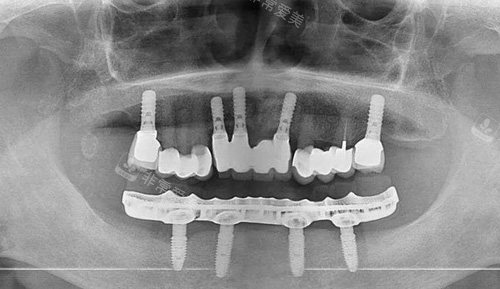

全口种植牙下颌